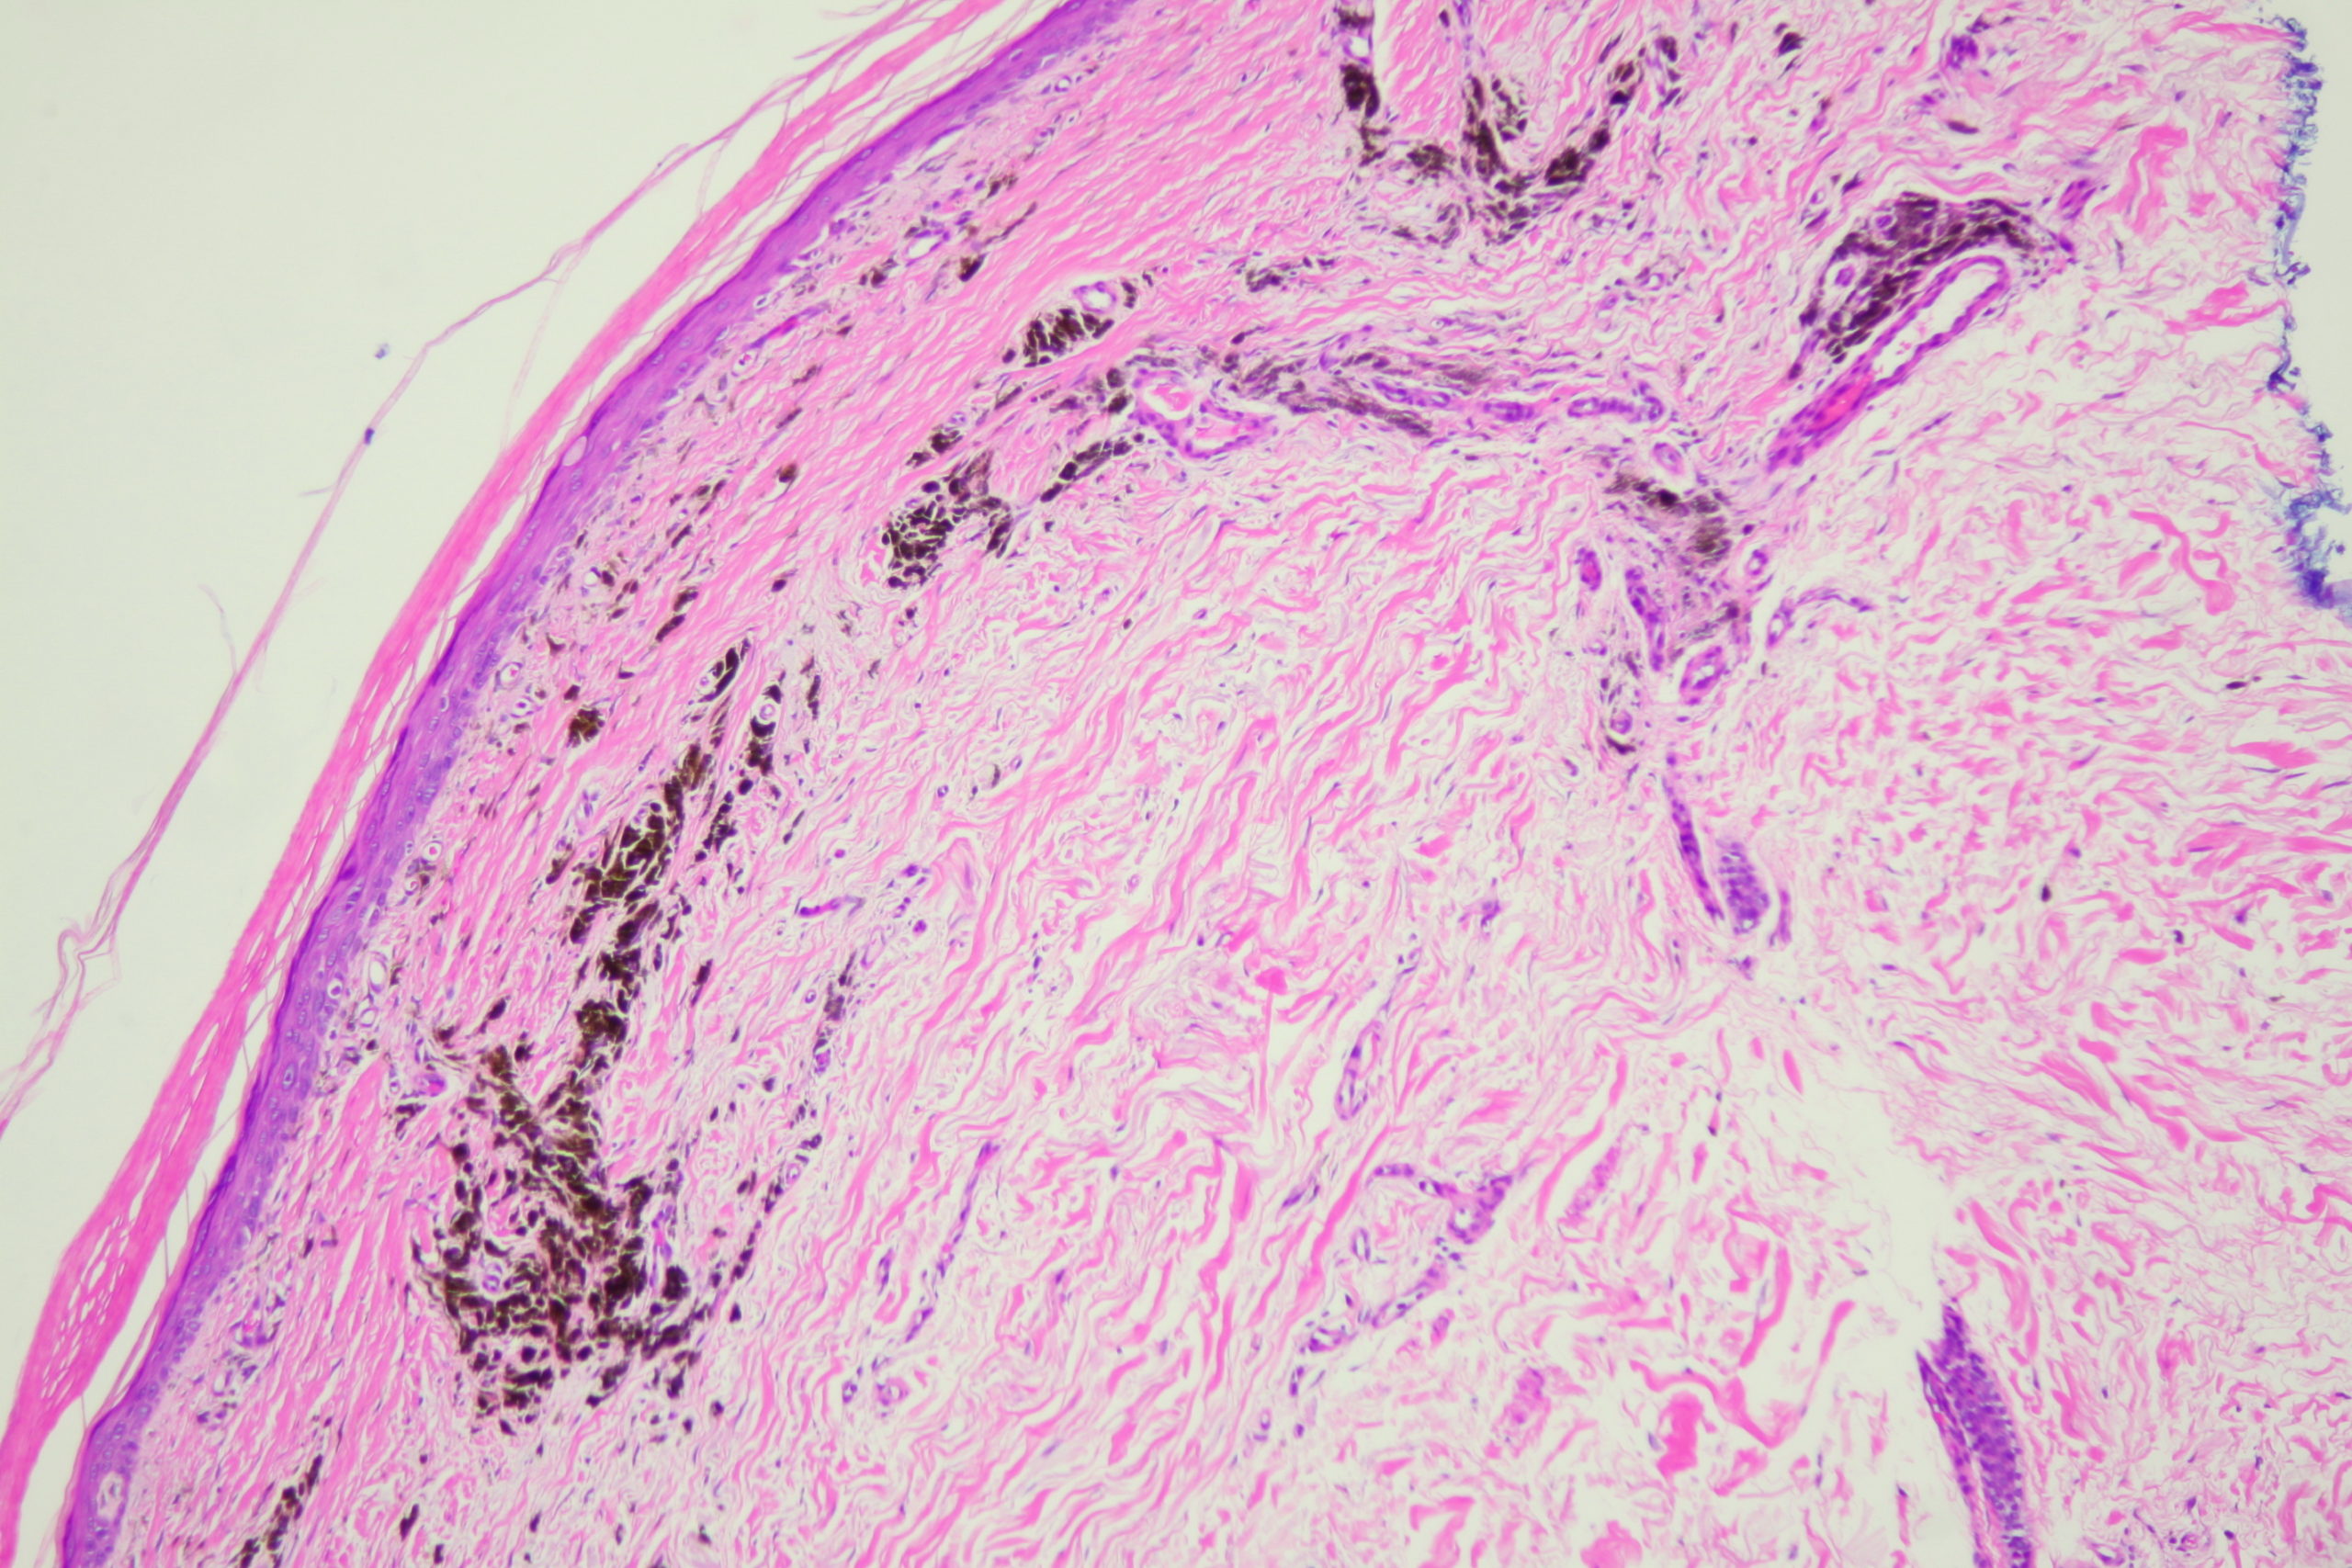

Site: Ankle

Diagnosis: Post Inflammatory Hyperpigmentation

These lesions arose after he went on Check Point inhibitor for metastatic melanoma. Note the perilesional hypopigmentation as well as the post inflammatory hyperpigmentation which was all that was left of his melanoma metastases. These had been stable for the last 9 months with no evidence in PET scans of melanoma elsewhere. This rteally shows the effectiveness of these immune stimulating drugs in metastatic melanoma.